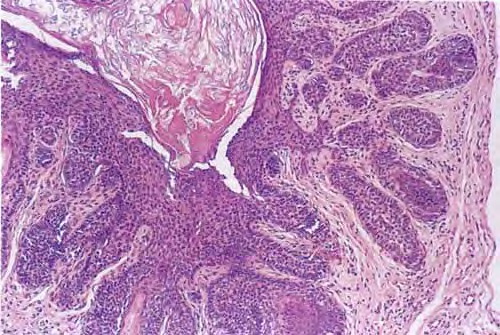

Read MoreTrichoepithelioma =ورم ظهاري شعري Trichoepithelioma Trichoepithelioma occurs either in multiple lesions or as a solitary lesion. The name trichoepithelioma is preferable to other designations, such as epithelioma adenoides cysticum and multiple benign cystic epithelioma, because it is more indicative that the differentiation of this tumor is toward hair structures. Multiple trichoepitheliomas are transmitted as an autosomal dominant trait (53). In most […]